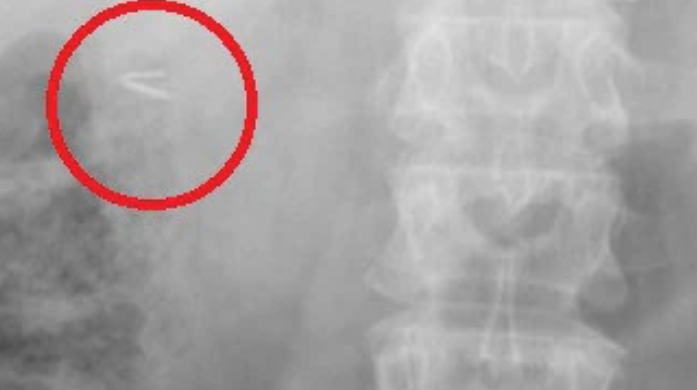

根據《ETtoday》報導,綜合外媒指出,手術遺留物品引起的醫療糾紛時有所聞,澳洲一名48歲女子納布爾西(Rouba Naboulsi)表示,她從2003年開始感覺腹部劇烈疼痛,求診無數次還是沒有辦法解決,根本找不到病因,2020年病情加重,痛到她無法進食,在家庭醫生的建議下,決定到醫院做核磁共振(MRI),卻在體內發現一個金屬物體,檢查也被迫中止,一查該物品竟是手術用的小夾鉗。

找出長期疼痛的根源,醫生檢視病例查出,應是1997年開刀切除膽囊時,夾子被遺留在體內,在這23年期間,夾子更從腹部移動到直腸附近,才讓她疼痛難耐,納布爾西氣得對雪梨西部奧本醫院(Auburn Hospital)提起訴訟,希望法官能替她主持公道!